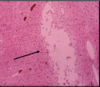

Necrotizing vasculitis